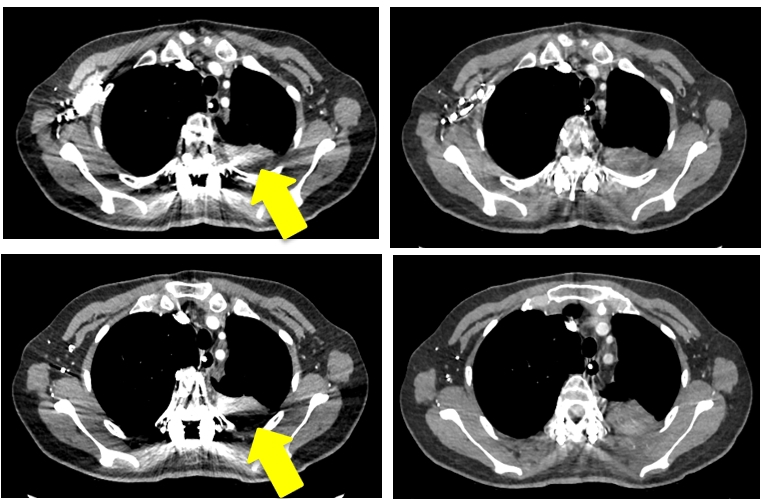

能谱去除金属伪影

综合使用CT能谱成像技术和MARs技术,能有效减除金属植入物引起的伪影,明显改善金属植入物周围组织结构的影像清晰度,使CT图像质量显著提高,给金属植入术后患者的复查和随访提供了很大的帮助,具有广泛的临床应用价值。